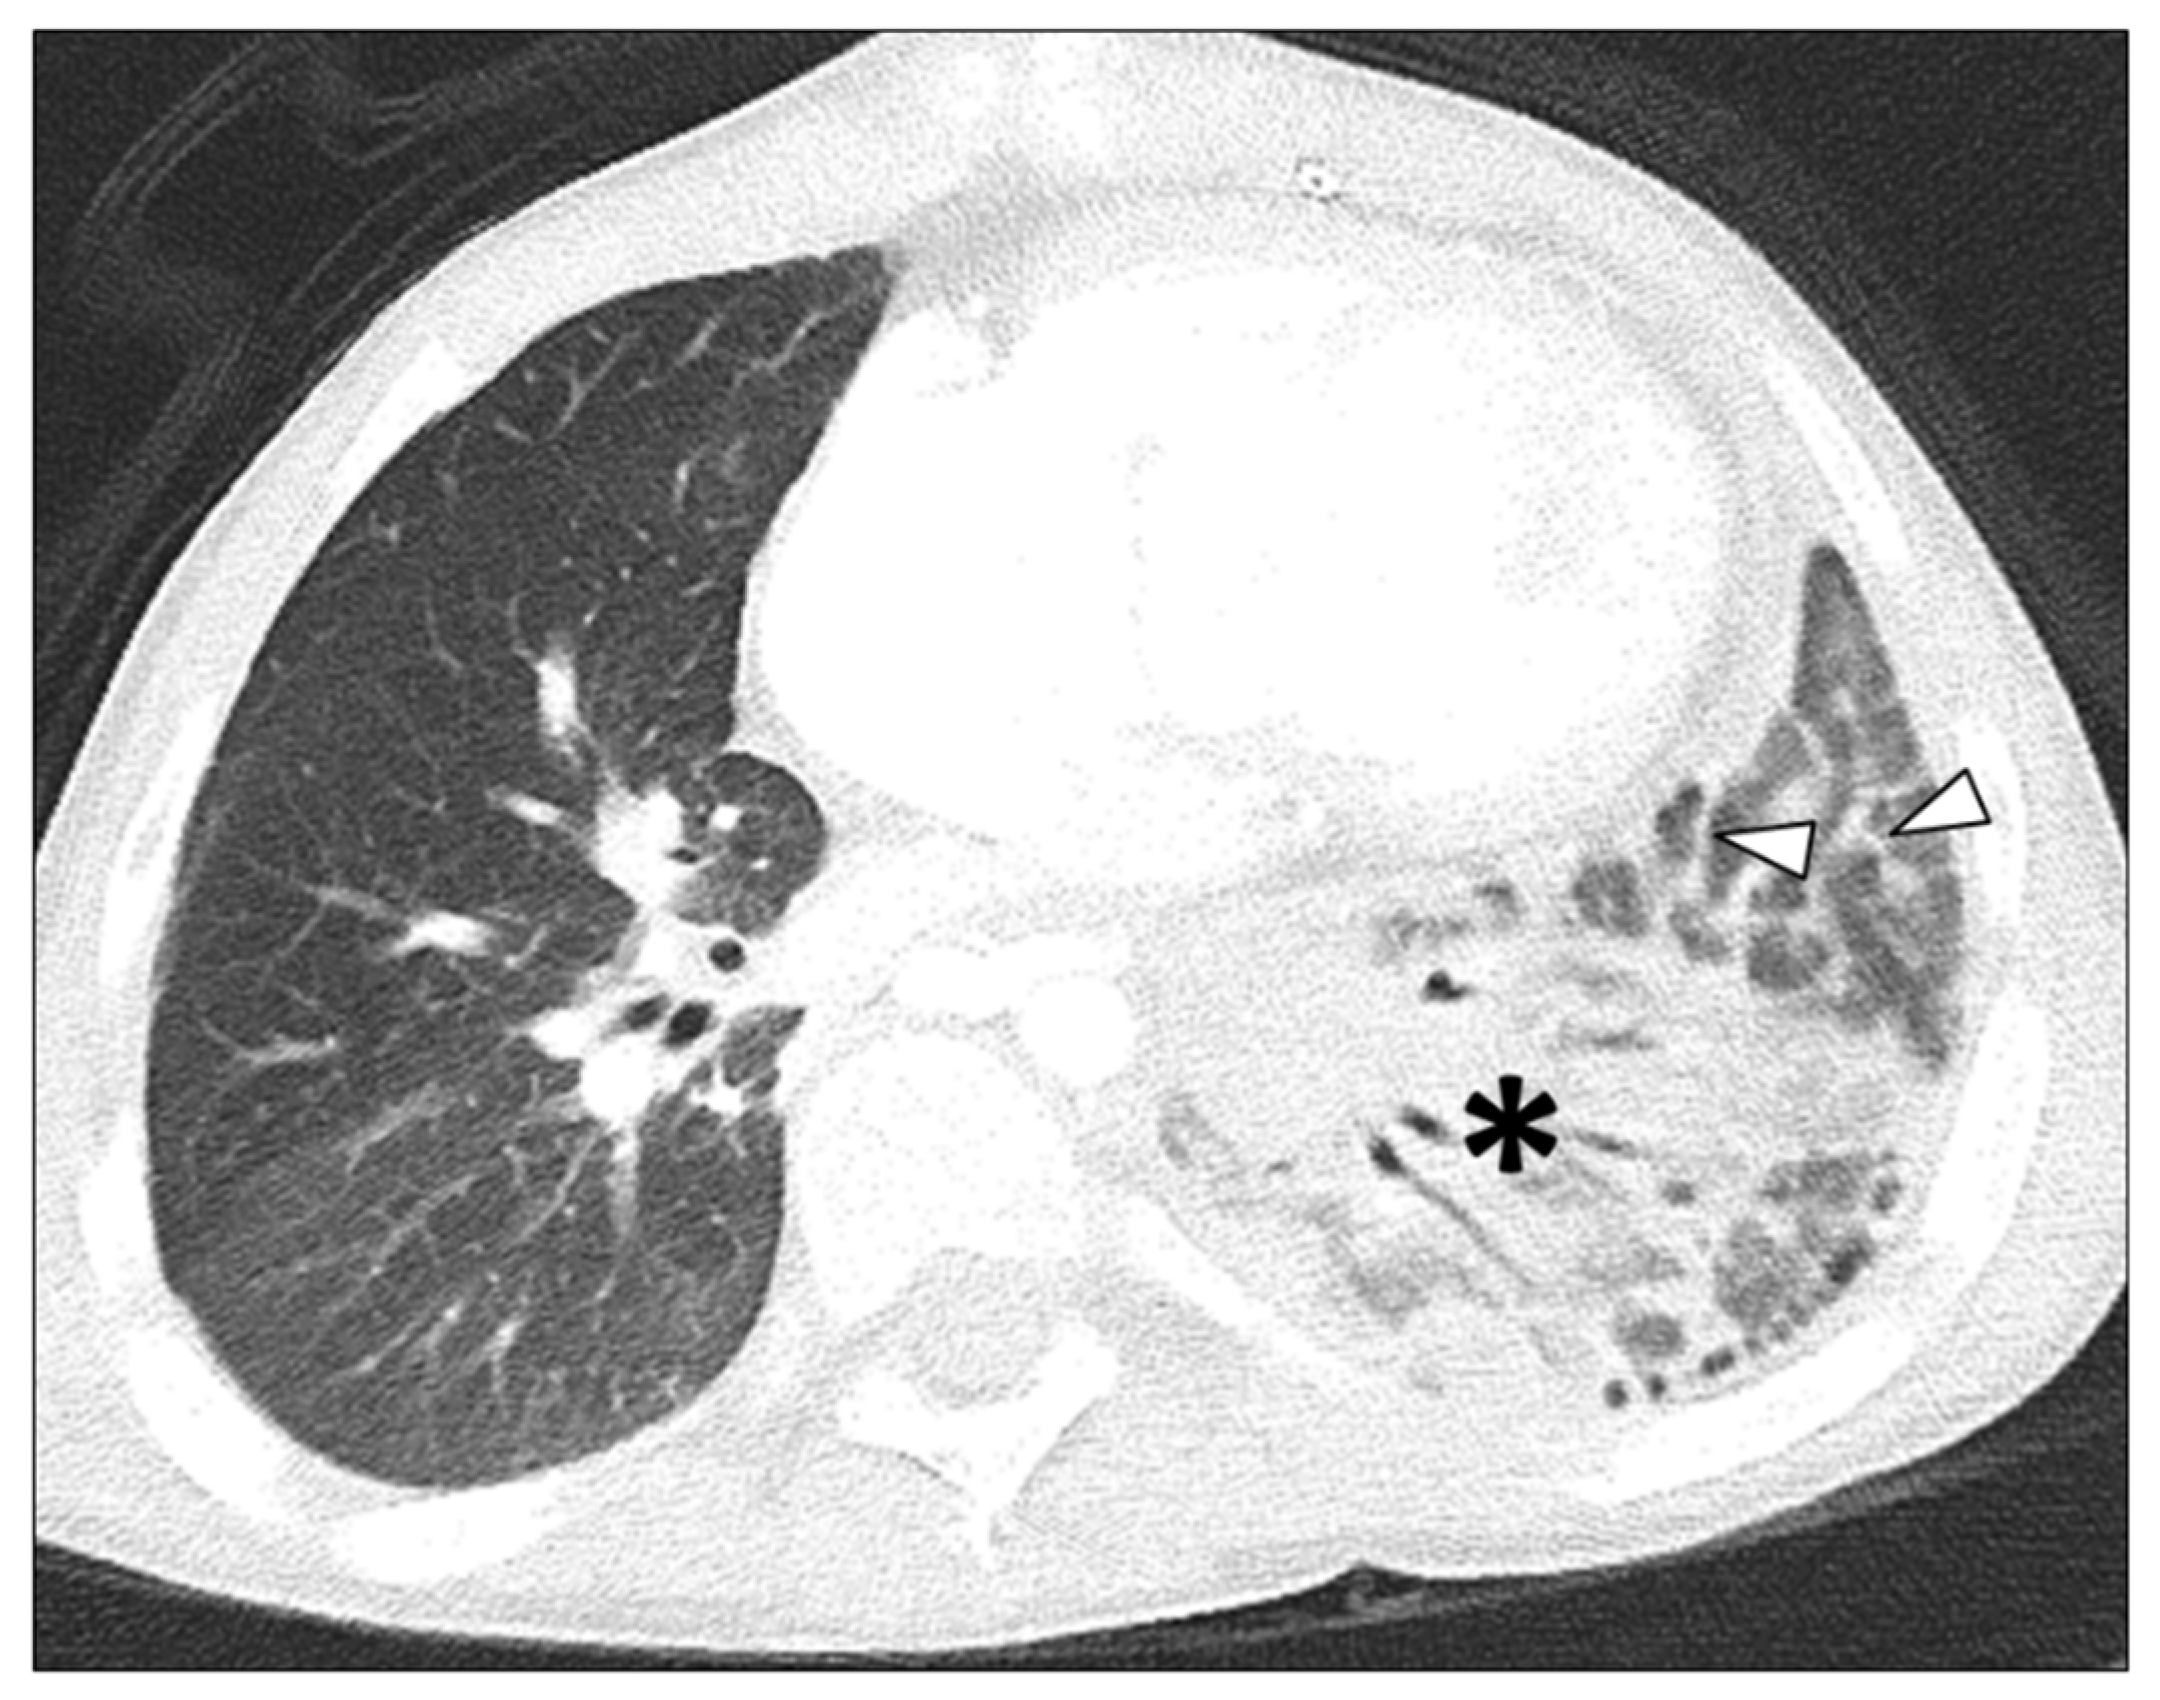

- Lee, E.Y.; Jenkins, K.J.; Vargas, S.O.; Callahan, R.; Park, H.J.; Gauthier, Z.; Winant, A.J. Thoracic multidetector computed tomography angiography of primary pulmonary vein stenosis in children: Evaluation of characteristic extravascular findings. J. Thorac. Imaging 2021, 36, 318–325. [Google Scholar] [CrossRef] [PubMed]

- Lee, E.Y.; Callahan, R.; Vargas, S.O.; Jenkins, K.J.; Park, H.J.; Gauthier, Z.; Winant, A.J. Extravascular MDCT findings of pulmonary vein stenosis in children with cardiac septal defect. Children 2021, 8, 667. [Google Scholar] [CrossRef]

- Lee, E.Y.; Vargas, S.O.; Jenkins, K.J.; Callahan, R.; Park, H.J.; Gauthier, Z.; Winant, A.J. Secondary pulmonary vein stenosis due to total anomalous pulmonary venous connection repair in children: Extravascular MDCT findings. Children 2021, 8, 726. [Google Scholar] [CrossRef] [PubMed]